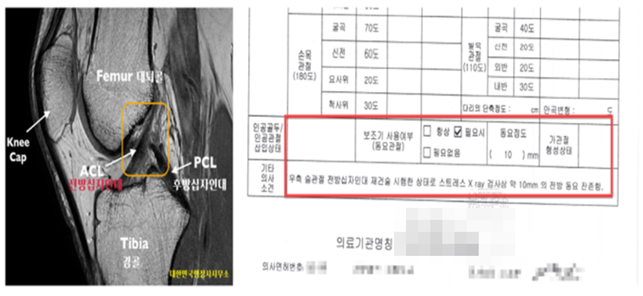

민간병원 및 국군수도병원 등지에서 MRI 등의 영상촬영을 통해

반월상연골전부파열, 전방십자인대

완전파열 소견과 관절내시경하의 재건술을 시행했습니다.

우측슬관절을 30도 전방당김 테스트를 실시해 본 결과

경험칙상 7~10mm 전방전위를 감지했습니다.

대학병원의 최종 진단결과,

'우측 슬관절 전방십자인대 파열로 전방십자인대 재건술'을 시행하였고,

정상적인 보행과 일상생활이 어려워해 스트레스뷰검사 등의

동요검사를 추가 확인되어 이에 보훈신청 및 국가장애등록을 진행했습니다.

관절 인대 손상에 의한 불안정성이 10밀리미터 이상인 경우에 해당됩니다.

전방십자인대가 파열된 경우에는 무릎관절을 약 20도 이상 30도 이하의 정도로 굽힌 상태에서

스트레스 방사선으로 촬영(기계를 이용해 스트레스를 부과하여 촬영하는 것을 말한다)하고,